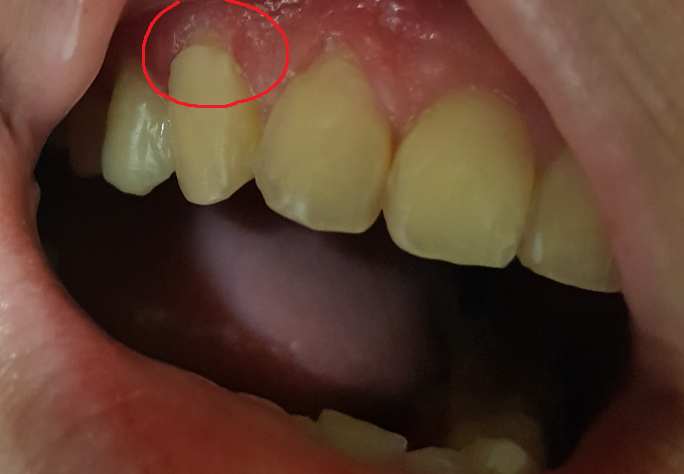

안녕하세요. 한달전쯤에 윗앞니를 중심으로 6곳, 치경부마모가 진행된 부위를 레진으로 수복치료하였는데요

잇몸에 피가 나도 참으면서 양치를 한게 원인인건지 수복치료한 곳에 잇몸이 더 올라가서 상아질이 다시 노출되버렸어요

사진으로 보았을 때는 레진으로 치료한 부위가 떨어진 것으로 보입니다. 현재 사진으로 보았을 때는 재 수복을 해주셔야 할 것으로 보입니다. 현재는 시리거나 불편감이 없지만 시간이 지나면 불편감이 계속해서 나타날 것으로 봉비니다. 따라서 치과 방문 후 해당 부위를 다시 수복하는 것이 좋아 보입니다.

우선 잇몸자체가 경미한 염증이 있는것으로 보입니다.

해당부위에 스케일링을 먼저 한 뒤에, 잇몸이 어느정도 치유되면 그때 다시 치경부마모증 치료를 하는게 좋아보입니다.